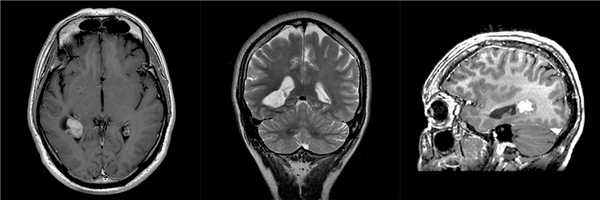

Пациент 37 лет страдает головной болью в течение нескольких лет. В связи с нарастанием частоты и интенсивности приступов головной боли выполнил МРТ, при которой выявлена опухоль заднего рога правого бокового желудочка.

![МРТ признаки ганглиоглиомы]()

При серийных сканированиях отмечается двукратное увеличение размеров опухоли. По данным ПЭТ-КТ головного мозга, индекс накопления радиофармпрепарата 1,6.

Проведена операция радикального удаления опухоли. Гистологический диагноз - ганглиоглиома.

В послеоперационном периоде отмечались расстройства глубокой и поверхностной чувствительности, нарушение схемы тела, практически полностью регрессировавшие к моменту выписки (8 сутки) на фоне консервативной терапии.

При контрольной МРТ через 1 год данных за рецидив опухоли нет.![Успешное хирургическое лечение ганглиоглиомы]()